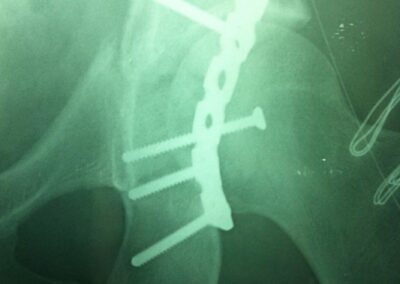

Η χειρουργική αποκατάσταση του ισχίου θα πρέπει να πραγματοποιείται όσο το δυνατόν πιο άμεσα μετά τον τραυματισμό. Τα εξωαρθρικά κατάγματα αντιμετωπίζονται με τη χειρουργική μέθοδο της οστεοσύνθεσης ή της ενδομυελικής ήλωσης.

Η θεραπεία που θα εφαρμοστεί εξαρτάται από τον τύπο του κατάγματος. Συνήθως εφαρμόζεται χειρουργική θεραπεία, εκτός από κάποιες περιπτώσεις απαρεκτόπιστων καταγμάτων. Η χειρουργική επέμβαση που πραγματοποιείται είναι η ημιαρθροπλαστική ή η ολική αρθροπλαστική ισχίου, ενώ κάποια κατάγματα ισχίου αντιμετωπίζονται με τη μέθοδο της οστεοσύνθεσης ή της ενδομυελικής ήλωσης.